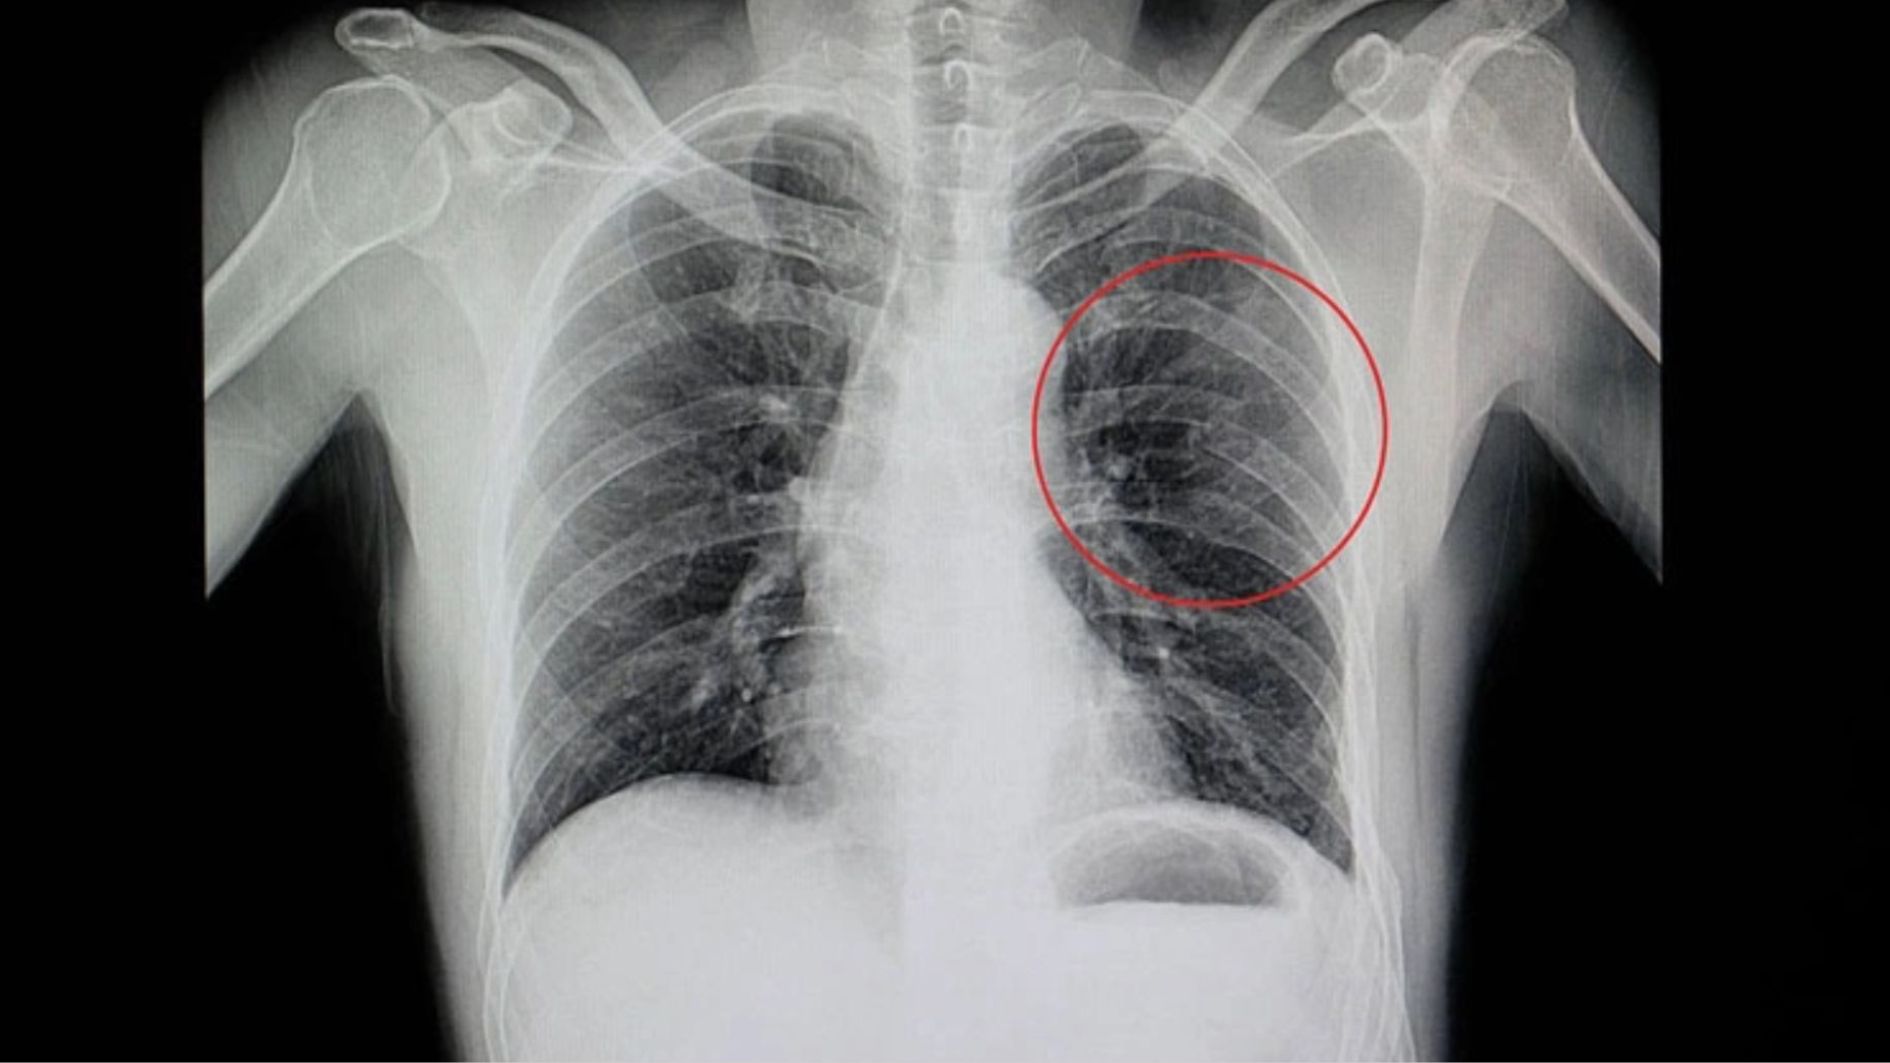

Qua thăm khám và các xét nghiệm hình ảnh như X-quang ngực hoặc CT-scan, bác sĩ sẽ đánh giá chính xác mức độ tổn thương và lựa chọn phương pháp điều trị phù hợp. Thông thường, điều trị bao gồm bất động vùng xương bị rạn, kết hợp giảm đau, chống sưng và bổ sung dinh dưỡng để hỗ trợ quá trình liền xương, giúp các triệu chứng đau và sưng dần thuyên giảm.